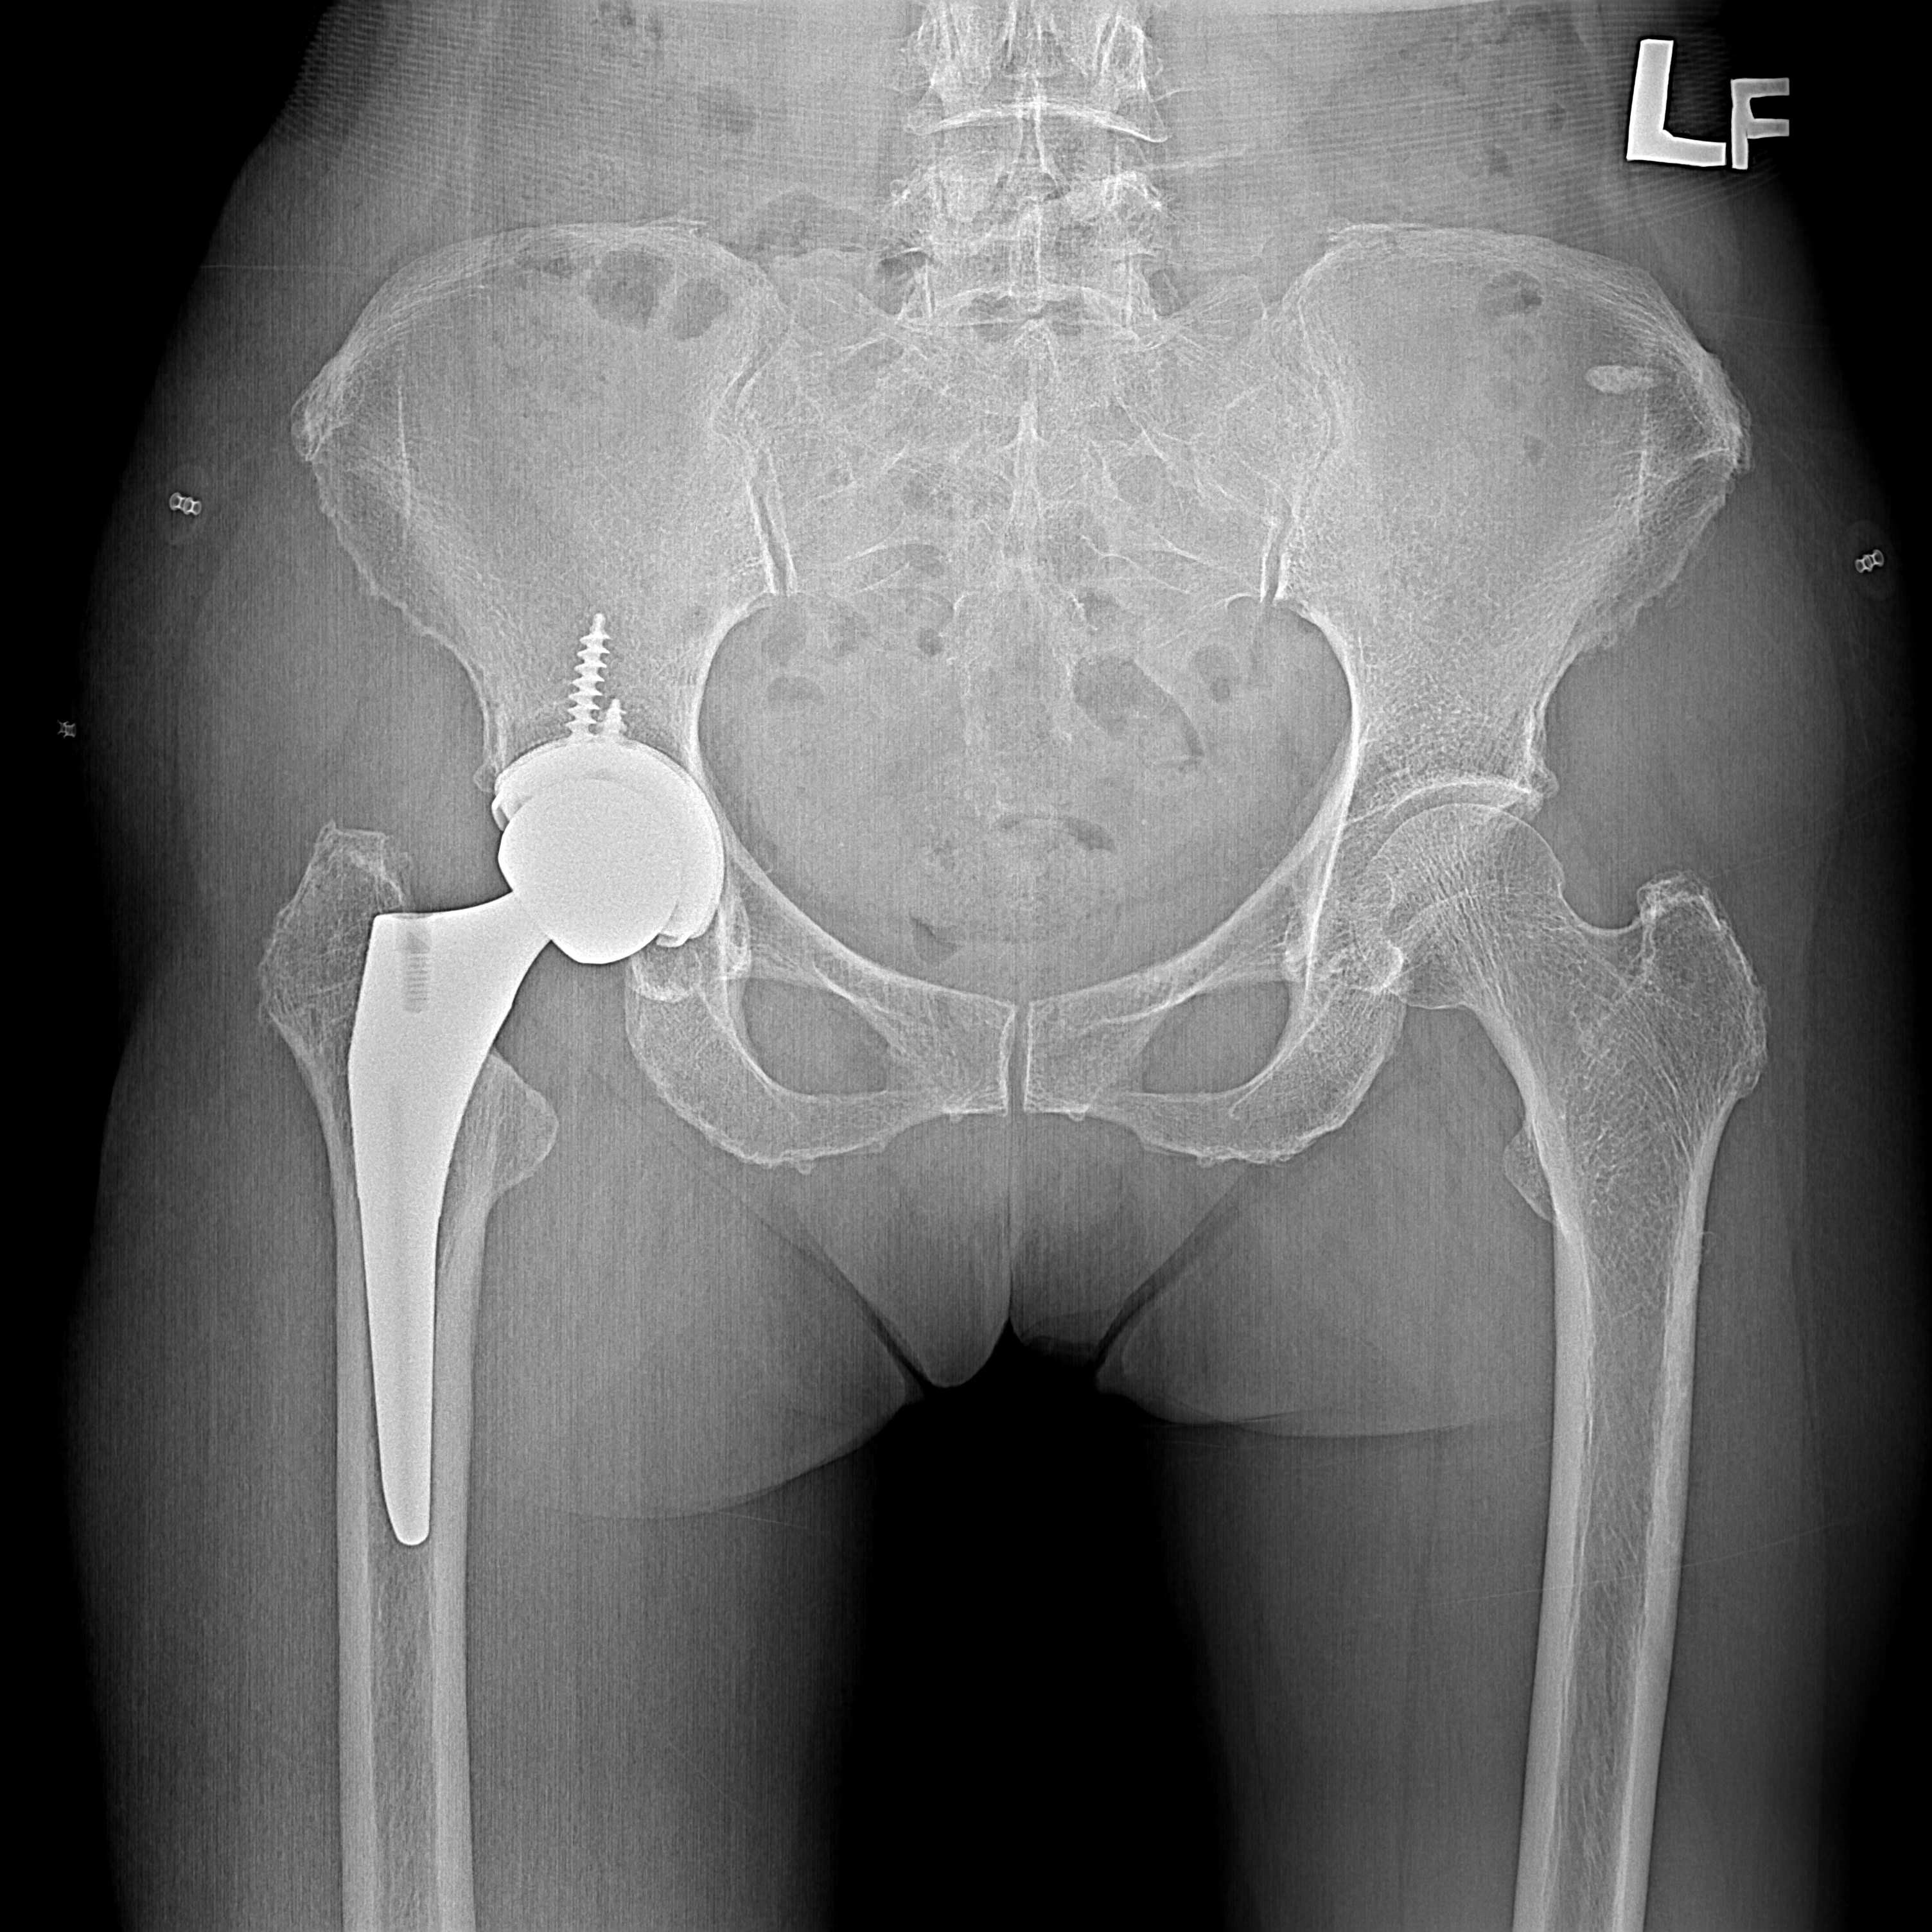

機器手臂手術 首頁 案例分享 髖關節手術 機器手臂手術 72歲 楊女士 退化性關節炎 術前 術後 60歲 彭先生骨股頭壞死 術前 術後 53歲 王女士退化性關節炎(DDH先天發育不全 CROWE TYPE 2) 術前 術後 83歲林女士退化性關節炎 術前 術後 83歲林女士退化性關節炎 術前 術後 楊女士 70歲 術前 術後 蔡女士 60歲 術前 術後